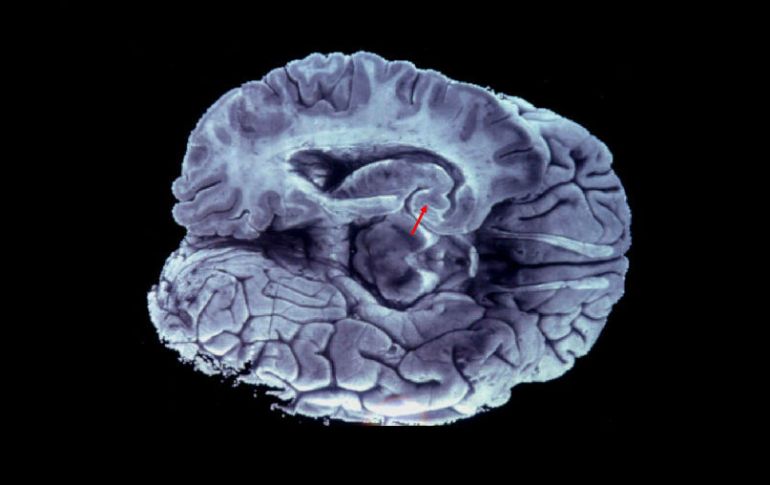

Tecnología | La impresión en 3D contribuirá al estudio de los trastornos propios del órgano Crean una réplica en tercera dimensión del cerebro humano La impresión en 3D contribuirá al estudio de los trastornos propios del órgano Por: EFE 1 de febrero de 2016 - 13:39 hs La geometría en el cerebro importa, pues al permitir que los pliegues se desarrollen en la adecuadamente se evitan enfermedades. EFE / ARCHIVO LONDRES, INGLATERRA (01/feb/2016).- Un equipo de científicos de Francia ha creado una réplica en 3D del cerebro humano con todos sus pliegues y cavidades, lo que contribuirá al estudio de los trastornos de este órgano y su funcionamiento interno, publica este lunes la revista "Nature Physics". En la revista, los investigadores detallan cómo crearon la estructura, elaborada con un gel elastómero rosa pálido, basándose en imágenes de cerebros de fetos humanos. El coautor del estudio, Jun Young Chung, subrayó que, a pesar de que no todos los cerebros humanos son iguales, sí que deben serlo "las dobleces para gozar de una buena salud". "Nuestro estudio muestra que, si una parte del cerebro o si la geometría que lo caracteriza no se desarrollan de forma correcta, podríamos no tener en el lugar correcto los pliegues y eso causaría transtornos", apuntó. Ayudados por investigadores de la Universidad de Harvard (Estados Unidos), los científicos señalan que lograron un modelo que supera las expectativas, pues los pliegues de gel son similares en tamaño, forma y orientación a los que se pueden ver en los cerebros de embriones. Chung remarcó que la geometría en el cerebro resulta de gran importancia, al permitir que los pliegues se desarrollen en la orientación adecuada y así se eviten problemas o enfermedades. Si bien las dobleces más pequeñas no se encuentran en esta estructura 3D, el modelo se puede reproducir para profundizar en investigaciones al presentar una escala y curvatura casi idéntica a la de un cerebro real. El proceso por el que se originan los pliegues en el cerebro se conoce como girificación y empieza durante la vigésima semana de gestación y se completa al año y medio de nacer. Durante este periodo de tiempo, la corteza cerebral se almacena en pequeñas cavidades con el objetivo de reducir la longitud de las conexiones neuronales. Temas Estudios científicos Ciencia médica Cerebro Tercera dimensión Lee También Julieta Fierro será homenajeada en la FIL INAPAM: ¿Cómo solicitar un turno para consulta médica gratuita? Nobel de Química premia el desarrollo de estructuras metal-orgánicas Nobel de Física para Clarke, Devoret y Martinis por descubrimiento sobre fenómenos cuánticos Recibe las últimas noticias en tu e-mail Todo lo que necesitas saber para comenzar tu día Registrarse implica aceptar los Términos y Condiciones